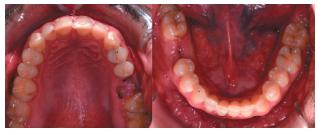

Caso clínico: se presenta el caso de un varón de 28 años, que acudió a consulta por la presencia de unos restos radiculares en localización de primer molar superior izquierdo. Se realizó un autotrasplante dental, siendo el diente donante el tercer molar superior izquierdo, que se trasplantó al alveolo del primer molar, mostrando buena evolución clínica y radiográfi ca.

Clinical case: a clinical case of a 28-yearold man is presented, who went to dental clinic for removal of left fi rst molar roots. An autotransplant was performed using left third molar as donor tooth, which was transplanted into fi rst molar alveolus, showing promising clinical and radiographic evolution.